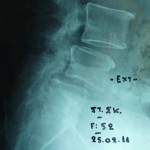

Εικονα 1: Προεγχειρητική πλαγία ακτινογραφία της Ο.Μ.Σ.Σ. σε ουδέτερη θέση και έκταση

Ο ακτινολογικός έλεγχος έδειξε ύπαρξη αστάθειας στην οσφυική μοίρα της σπονδυλικής στήλης (Επίπεδα Ο4-Ο5 / Ο3-Ο4) συνεπεία σπονδυλολισθίσεως, εκφυλιστικής αιτιολογίας. Αποφασίστηκε η χειρουργική αντιμετώπιση του προβλήματος με διαδερμική σπονδυλοδεσία (Κλειστή μέθοδος τοποθετήσεως των υλικών της σπονδυλοδεσίας).